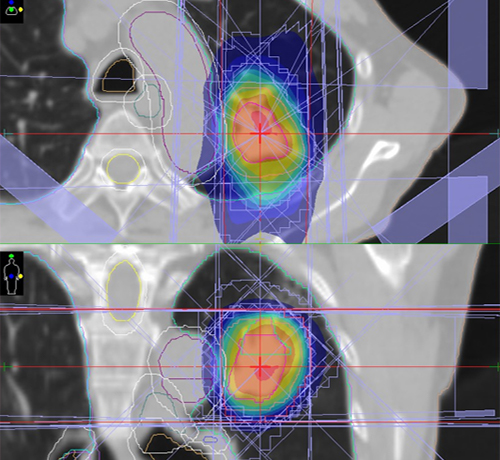

定位放射線治療 (SRT)

胸部や腹部の病巣に対し、多方向から高精度に集中させて放射線をあてる治療法で、周囲の正常組織へあたる線量を抑えることが可能です。

画像誘導放射線治療 (IGRT)

照射の直前や照射中に得られる患者さんの画像情報(X線画像等)を基に日々の放射線治療時の位置誤差を補正しながら正確に治療する技術です。